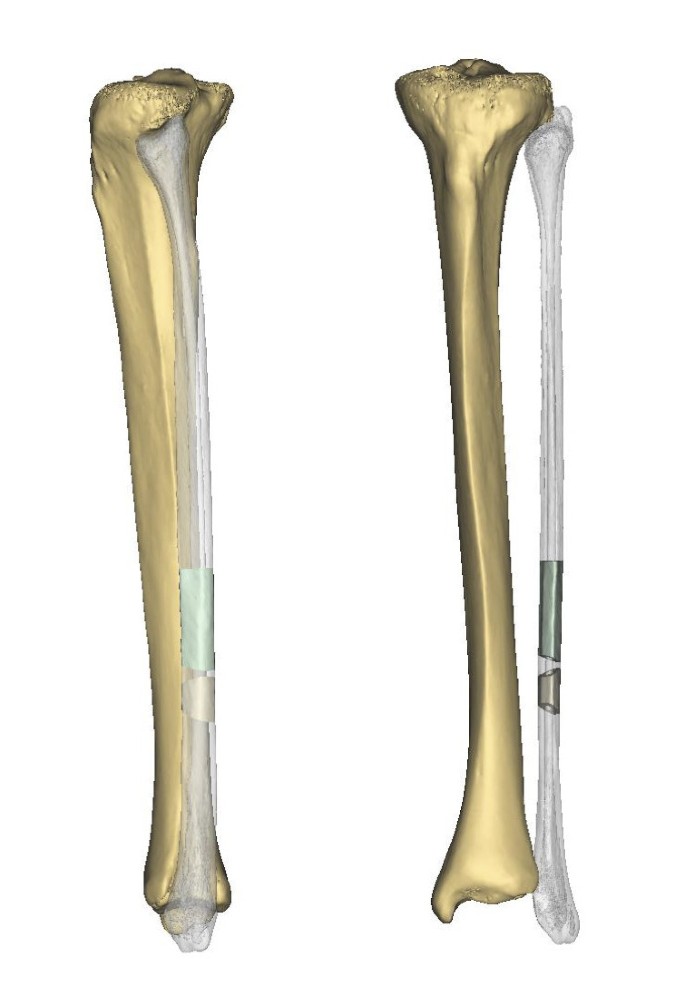

Анатомия фибулы: Подробные фотографии и схемы